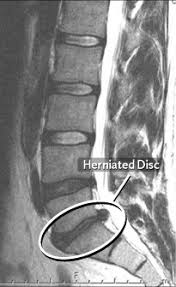

所以必須利用更精密的電腦斷層掃描檢查 (CT) ,顯現椎間盤突出有無壓迫影響到神經,另外醫師可能加作脊髓腔造影,需在蜘蛛膜下腔注射入顯影劑,如此可以加強脊索及神經根之影像,增加診斷之正確性。

現在醫師也可能是安排磁振造影檢查 (MRI) ,可將脊椎、脊髓、神經根、軟骨等 結構顯露無遺,找出那個部位有椎間盤突出 . 此項檢查就不需要打顯影劑。